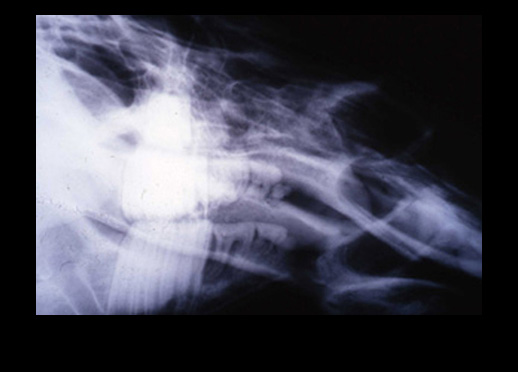

The WEDGE® is a one-piece, radiolucent mouth prop. The patented, anatomic design holds the carnivore mouth open during anesthesia by securely engaging the premolars and molars.

"The (Scheels) Veterinary mouth prop's biggest asset is its simplicity - open the mouth and stick it in!...it does not interfere with radiographic detail, can be ultrasounded, and autoclaved...can be used for dental and oral surgery procedures...is positioned within the mouth, unlike the spring loaded (extra-oral) devices which can be in the way of the operator and interfere with positioning the patient..."